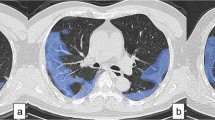

QCT was carried out on all CT scans. FACT-Digital lung TM software (DeXin, Xi'an, China) was used to perform fully automated three-dimensional CT quantitative measurements. The steps of segmentation were briefly undertaken as follows: (1) segmentation of the whole lung: a well-established thresholding operation was used to extract the lung volume. The threshold is determined based on intensity histogram analysis of the CT images; (2) segmentation of abnormal opacity: it was conducted by means of a 3D region-growing algorithm and a histogram-based thresholding technique; (3) bronchus and pulmonary vessels were segmented: a differential geometric approach was applied to automatically segment the vascular tree and airway tree. A “puzzle game” procedure acting as a “correction” operation for filtering false identifications was utilized; (4) quantitative evaluation of lesion’s volume was conducted after segmentation. The quantitative parameters included the lung volume (LV), total lesion volume (TLV), and percentage of abnormal opacity volume (lesion%). The pixels in abnormal opacity were processed with histogram analysis including an illustration of pixel attenuation (CT numbers). Histogram analysis also allowed measurements of mean density (MD) and the proportion of pixels related to ground-glass opacity (GGO). The details of the algorithm used in the software have been reported in previous studies ([12,13,14,15]; see Fig. 1).

Of 52 images, 42 were classified in level 1 (Fig. 2) and 8 were in level 2 (Fig. 3). No case was found in level 3. Two cases had negative findings on chest CT, who were both identified by radiologists and QCT. The time required to process one chest CT was 5 min.

QCT provides quantitative parameters to assess both extent and density of abnormal opacity. The range of percentage of lung involvement was herein 0–36%. The density of the lesion was assessed by CT value histogram. The CT patterns of GGO, GGO with crazy-paving pattern and consolidation exhibited to have different density characteristics and overall distribution characteristics (Fig. 4). According to the distribution of CT value histogram, we not only observed the average density, but also the density distribution below − 450 HU to describe GGO.